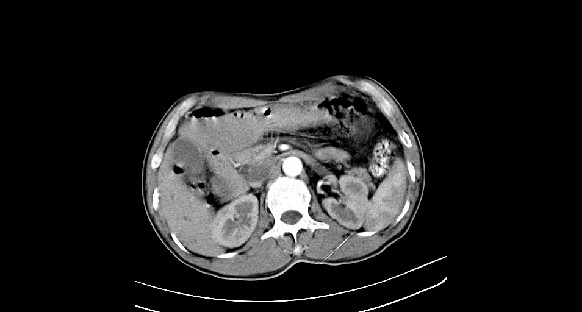

男性,70岁,体检b超发现左肾占位,请各位战友发表一下观点

左肾有两个病灶,且较大的病灶内可见点状钙化灶,增强扫描边缘也是呈渐进性强化,中央部分未见明显强化

肾癌较肾aml可能大,建议mri,若t2明显高信号者则肾癌基本诊断明确。